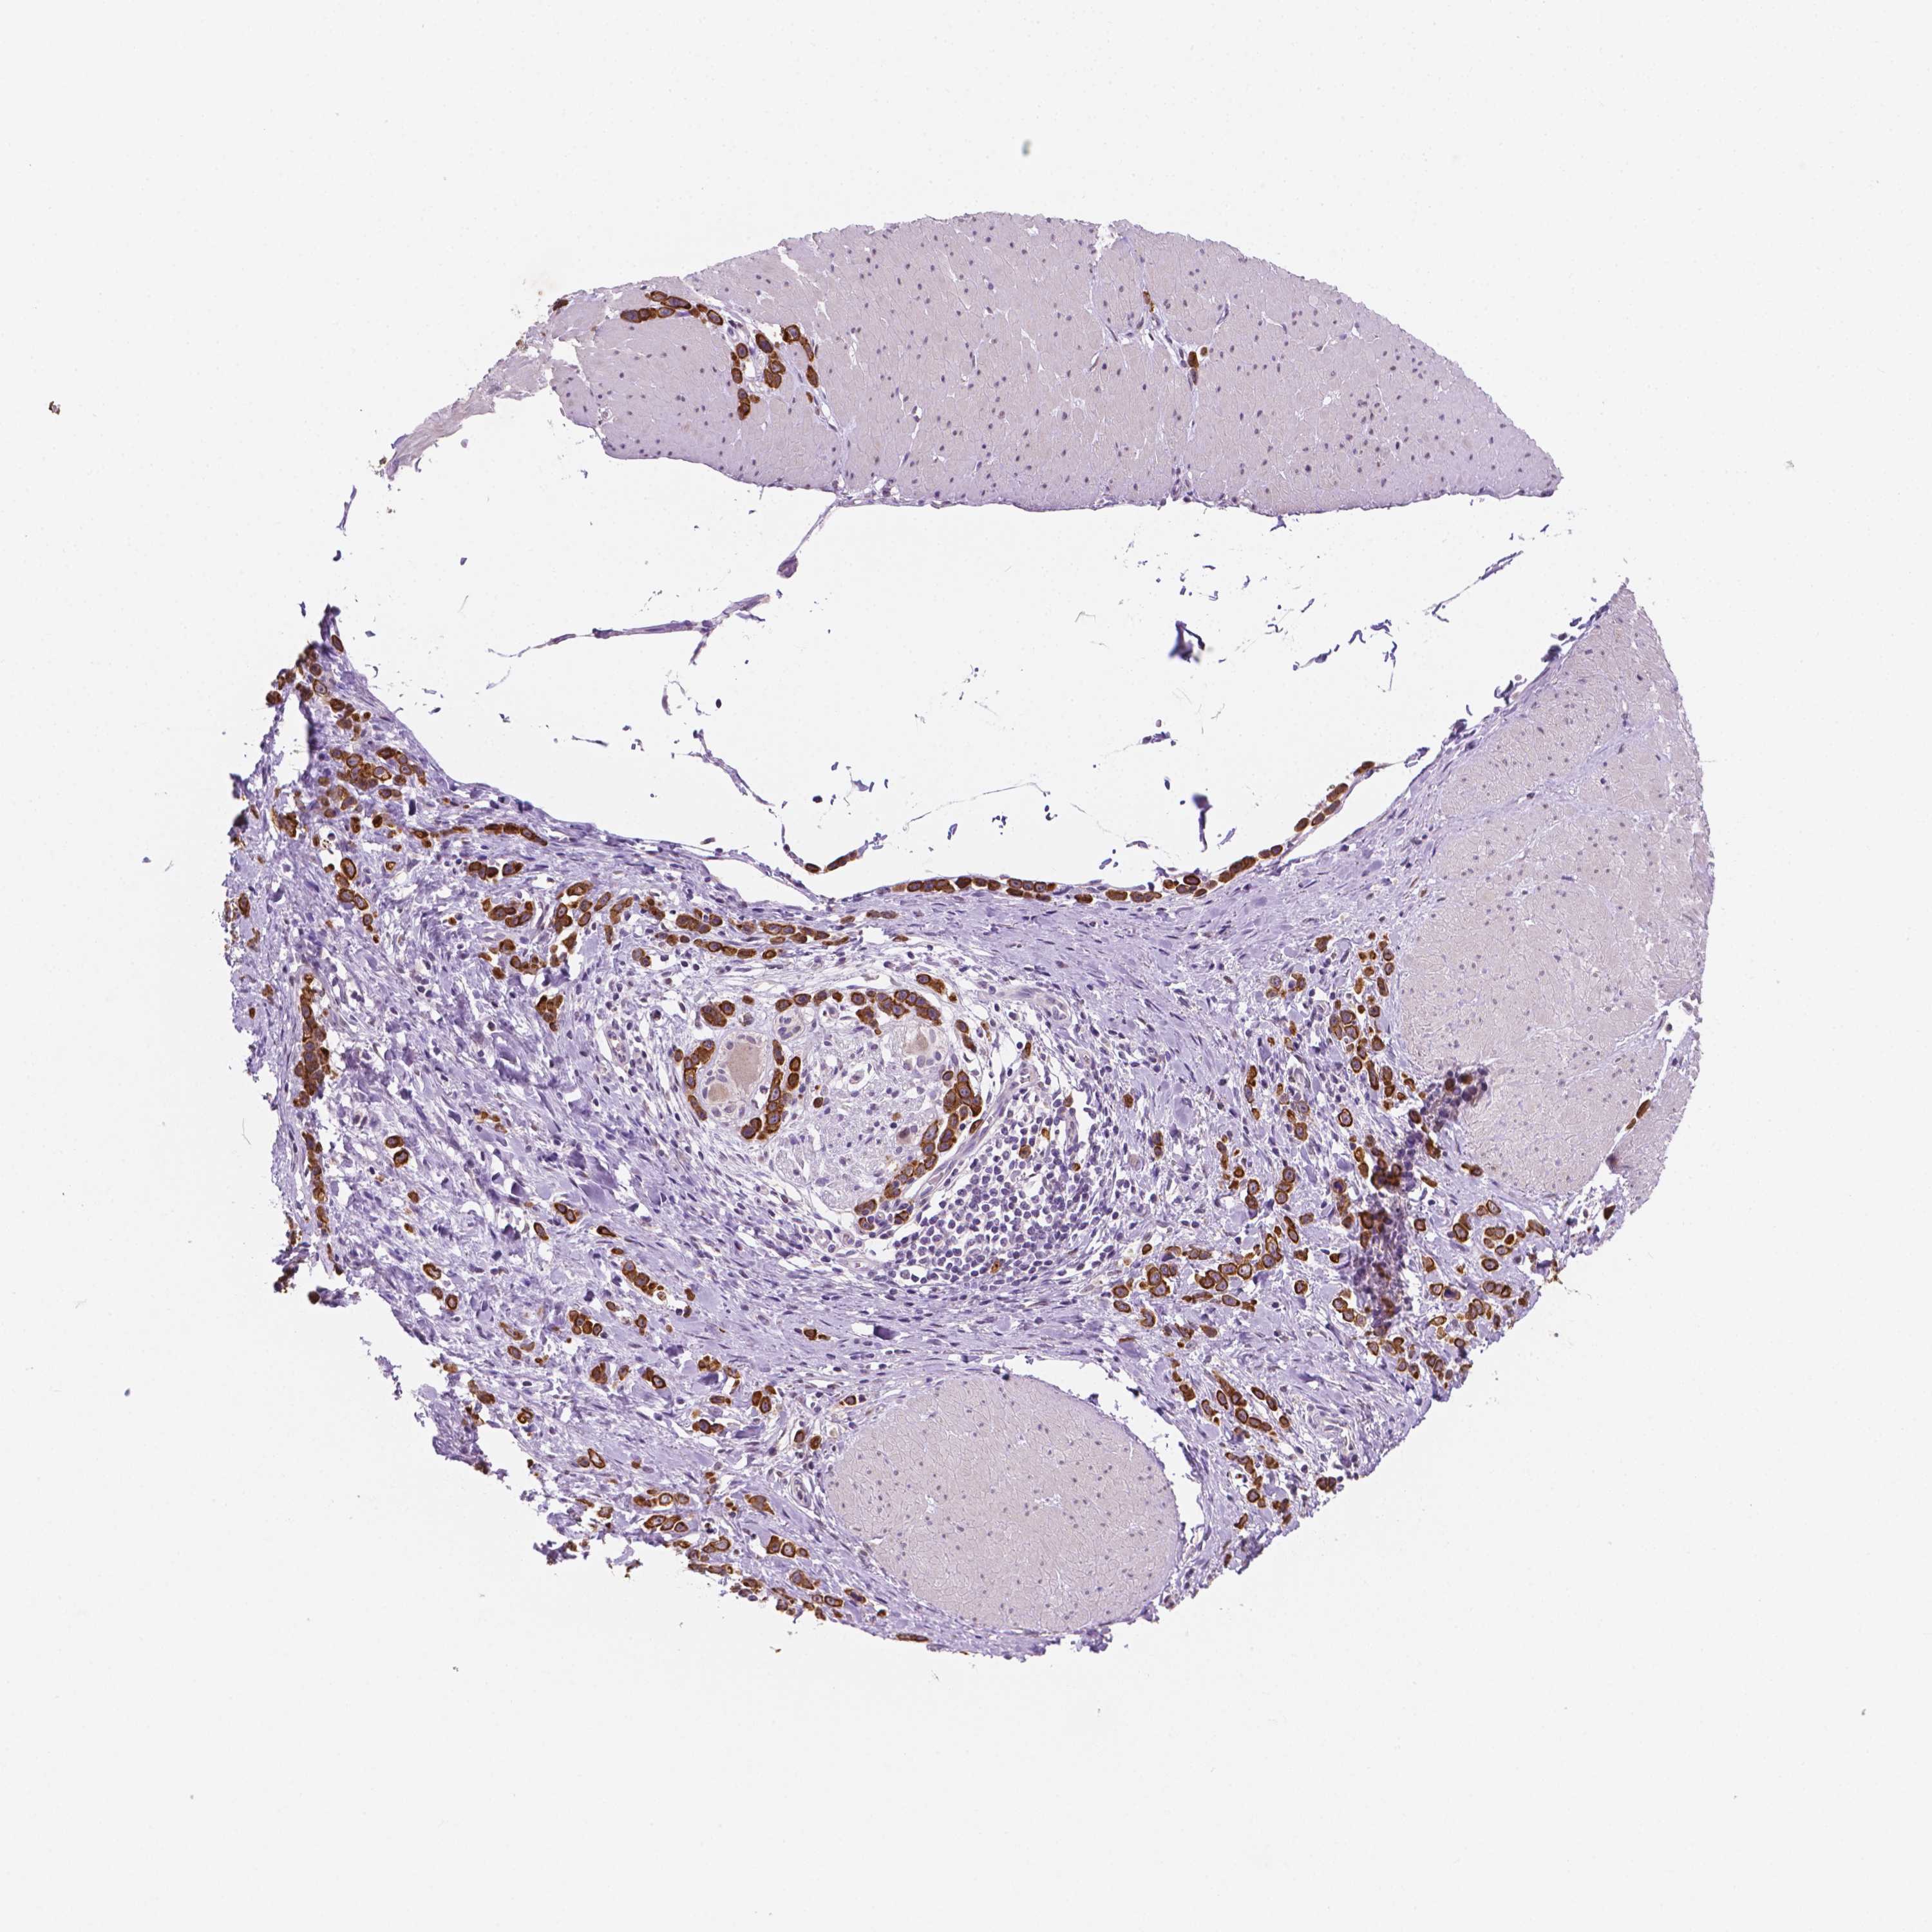

STOMACH CANCER - Protein expressioni

A mouse-over function shows sample information and annotation data. Click on an image to view it in a full screen mode. Samples can be filtered based on level of antibody staining by selecting one or several of the following categories: high, medium, low and not detected. The assay and annotation is described here.

Note that samples used for immunohistochemistry by the Human Protein Atlas do not correspond to samples in the TCGA dataset.

Antibody stainingi

Antibody staining in the annotated cell types in the current human tissue is reported as not detected, low, medium, or high, based on conventional immunohistochemistry profiling in selected tissues. This score is based on the combination of the staining intensity and fraction of stained cells.

Each image is clickable and will lead to virtual microscopy that enables deeper exploration of all samples and also displays staining intensity scores, fraction scores and subcellular localization as well as patient and tissue information for each sample.

Antibody HPA068764

Staining

High

Medium

Low

Not detected

Intensity

Strong

Moderate

Weak

Negative

Quantity

>75%

75%-25%

<25%

None

Location

Nuclear

Cytoplasmic/membranous

Cytoplasmic/membranous,nuclear

Adenocarcinoma, NOS